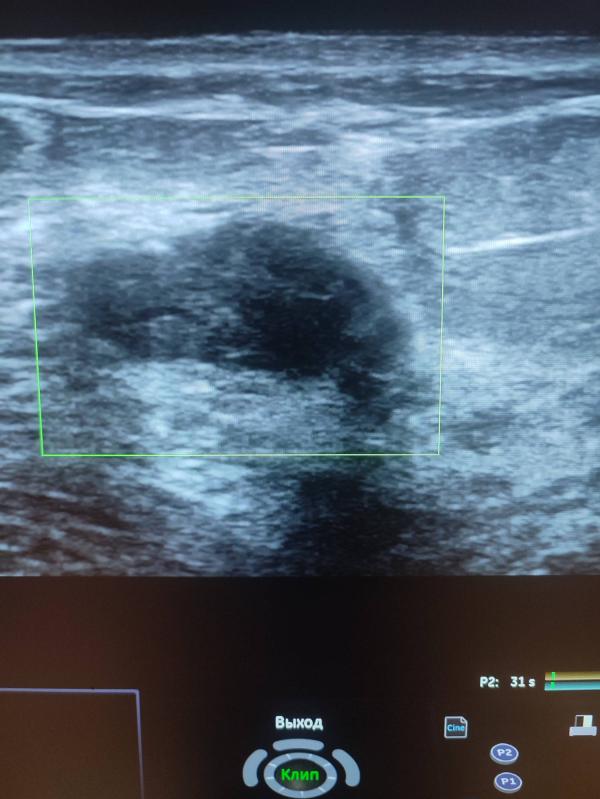

Добрый день девочки ! Хочу рассказать случай из практики: вчера у меня на приеме была девочка , возраст 31 год, планово готовилась на ЭКО, замужем 3 года! При УЗИ молочных желез было выявлено вот такие образования- точнее сказать рак левой молочной железы! В данном случае ни о какой беременности речи быть не может, тем более ЭКО ! Здесь длительное лечение , с последующей долгой реабилитацией! Самое интересное ,что она уплотнения отмечала давно , но к врачу не ходила ! (((